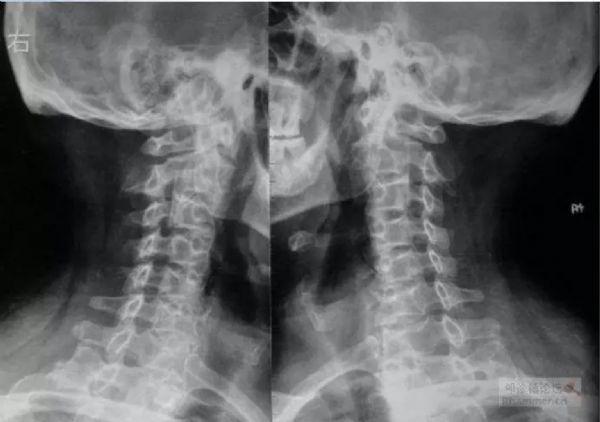

颈椎病骨质增生图片,颈椎骨质增生x光片

颈椎病概念 颈椎病是指颈椎间盘退行性病变, 颈椎骨质增生及其邻近

颈椎片:骨质增生

目前在临床上也是发病率比较高的,颈椎是骨质增生的易发部位,尤其是一

颈椎骨质增生x光片